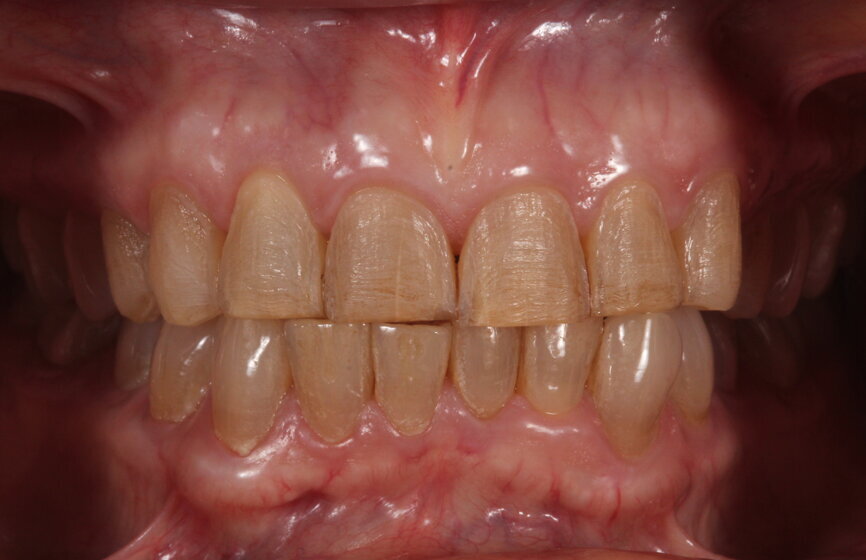

Fig. 24: Postoperative frontal smile.

At the delivery appointment, an aesthetic try-in was done prior to bonding the restorations. The patient approved the aesthetics, marginal fit was verified, and the teeth and restorations were etched and bonded (Variolink Esthetic, Ivoclar Vivadent). The patient was extremely satisfied with the treatment outcome (Figs. 22–25). An occlusal guard was provided as part of the treatment plan. At the one-year follow-up, the patient reported no complications.